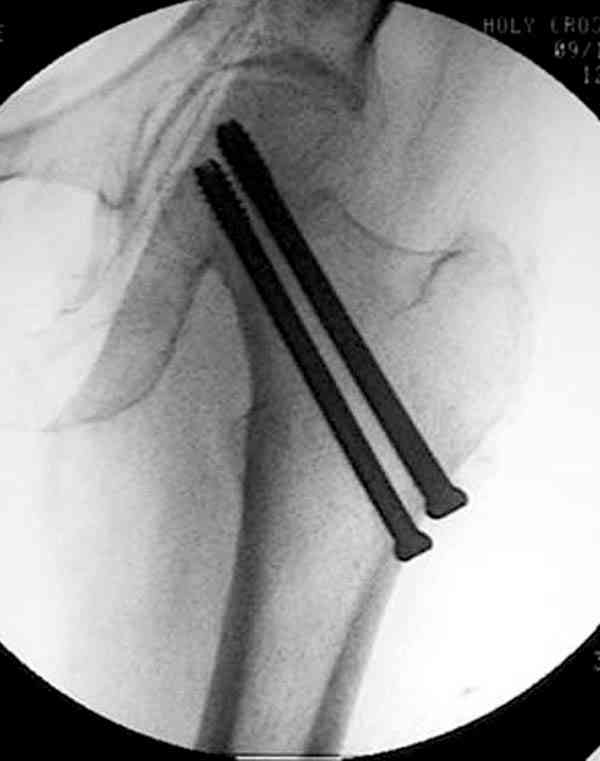

Коллега Челноков прав, здесь еще имеется риск перелома за счет ослабления латерального кортекса. Во время установки канюлированных шурупов за редким исключением спица вводится с одного раза, множественные попытки ослабляют латеральный кортекс, что станет источником перелома в этом месте.

В идеале для профилактики рефрактуры шурупы надо вводить не больше, чем под 130 градусным углом и не ниже уровня малого вертела.

Насчет биомеханических преимуществ одного шурупа тоже возникает вопрос. Если придерживаться канонов механики, для перелома шейки необходимо 3 паралельных шурупа, расположенных ближе к кортикальному слою шейки.

Здесь случай перелома из-за ослабления латерального кортекса через 3 недели после операции на шейке. Шурупы были установлены под большим углом, слабый латеральный кортекс не выдержал нагрузку.